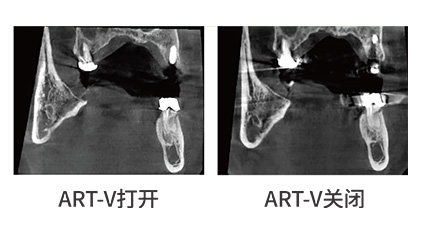

运动伪影和金属伪影的产生会阻碍影像画面的诊断数据。然而,PA集团官网自主研发ART-V去伪影技术,这项技术将有效减少了伪影的产生,从而提供给用户清晰可见的影像数据。